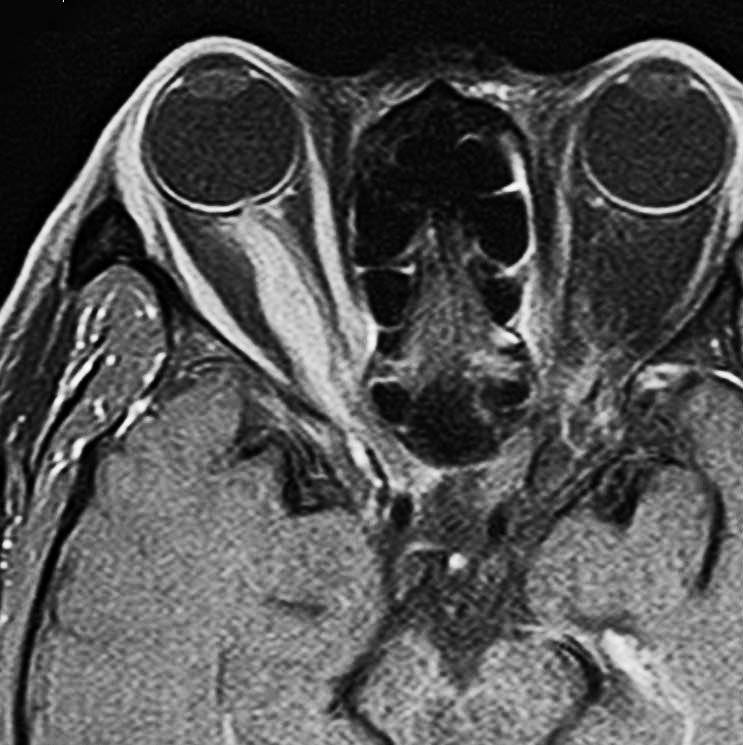

視神経鞘髄膜腫 optic sheath meningioma

眼窩内腫瘍です。視神経を包むし神経鞘から発生して,視神経鞘に沿って進展して増大します。視神経を圧迫してゆっくり症状が出ます。片目の視力が落ちるというのが症状ですが気づかれず発見が遅れることが多いでしょう。眼底検査で,初期には視神経乳頭 optic discの腫れが見られ,視力が悪化していくと視神経萎縮となります。眼底検査で動静脈シャントが見られるのも特徴的で,視力低下と視神経萎縮と併せてHoyt-Spencer triadと言われました。視力がほぼ消失するまで腫瘍が増大すると,眼球が前に押されて,眼球突出 exophhalmus, enophthalmus という症状が出ます。

治療は手術摘出ですが,この腫瘍を摘出するとほぼ確実に片眼の視力を消失します。ですから視力が無くなるまで手術は待機するという考え方が一般的です。数年以上視力があまり低下しないで腫瘍も増大せず経過する患者さんもいます。視力温存目的で治療するなら,視力の良いうちに定位放射線治療を行うべき疾患です。だからといって何でも定位放射線治療をすればよいというものではありません。問題は,視神経管から鞍結節に腫瘍が伸展している例があるということです。ここを放置すると反対側の健常な眼の視力が侵されることになりかねないので慎重に判断します。

比較的急速に視力低下して手術摘出した例

右目が暗いという症状で発症して,眼科では視神経乳頭腫脹とわずかな視野欠損だけで発症した患者さんです。3年間観察されましたが,その間には眼底所見も視力 Vd 1.2 も変化がなかったとの眼科からの報告です。そのすぐ後で患者さん本人は,右目が暗くなる回数が増え、視野狭窄があり軽い眼球突出,まわりがぼやけてますが中心は1.0見える状態との訴えで相談を受けました。主治医の先生の方針では経過観察ということで,まだ視力も良いので私もそうした方がよいと同意したのですが,その後半年くらいで視力が手動弁まで低下してしまいました。眼球運動と右眼球を温存するために腫瘍を摘出しました。

左側は,摘出標本の輪切りの写真です。この部位は腫瘍の発生した部位ではありません。一番外側にみえるのは視神経鞘 optic sheathという膜です。その内側が髄膜腫で,その内側が視神経です。すなわち髄膜腫は,視神経鞘と視神経の間のくも膜下腔を,這うように伝わって増殖伸展しています。このくも膜下腔には視神経への栄養動脈や網膜動脈も入っているので,この腫瘍だけを視神経や細動脈を傷つけずに摘出することはできないのです。